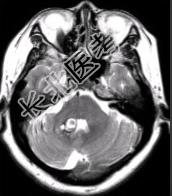

- [材料题] 患者女,41岁。头痛半年,加重10d。头部MRI显示如下图。

- 简答题2、根据该病的影像学表现,该患者可能的诊断是什么?

- 简答题3、为进一步确定诊断,请问下一步的影像学检查是什么?

- 简答题4、MR增强检查如下图。请问最可能的诊断是什么?